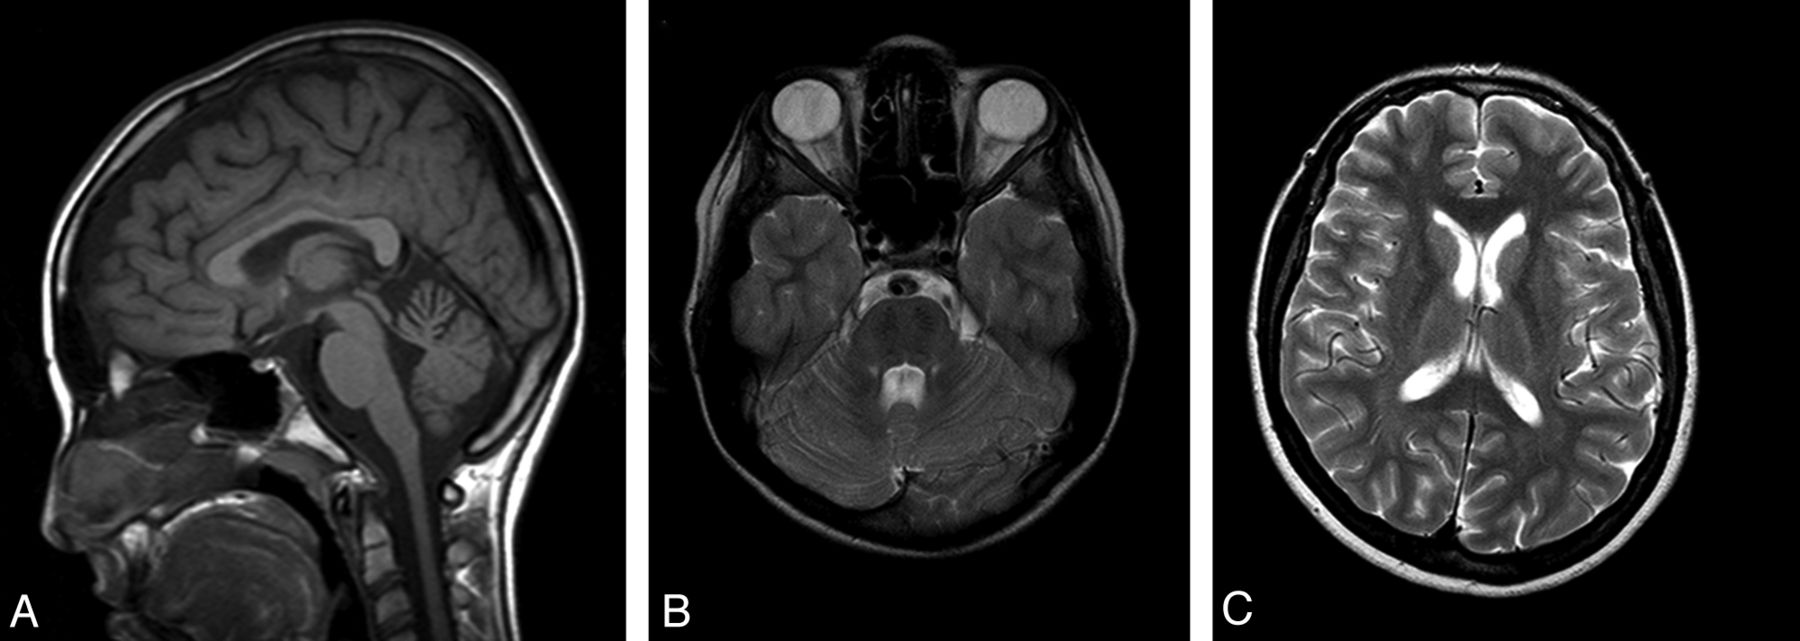

Structural MR Imaging

All patients showed superior vermian atrophy (Fig 1A) and bilateral parallel and paramedian T2-hypointense stripes in the pons (Fig 1B). Atrophy of the brain stem (n = 4), the cerebellar and cerebral hemispheres (n = 3), and bilateral T2 hyperintensities in the lateral thalami (n = 4) were observed (Fig 1C). On T2*gradient recalled-echo imaging, no patient had susceptibility signal change.

Sagittal T1-weighted spin-echo (A), axial T2-weighted fast spin-echo (B,C) images of a 14-year-old patient show atrophy of the superior vermis (A) and bilateral, paramedian, T2-hypointensite stripes (B) and bilateral, linear T2 hyperintensities in the lateral thalamus (C).